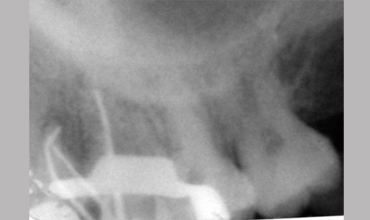

MB2

Management Of Maxillary First Molar With Mb 2 Canal